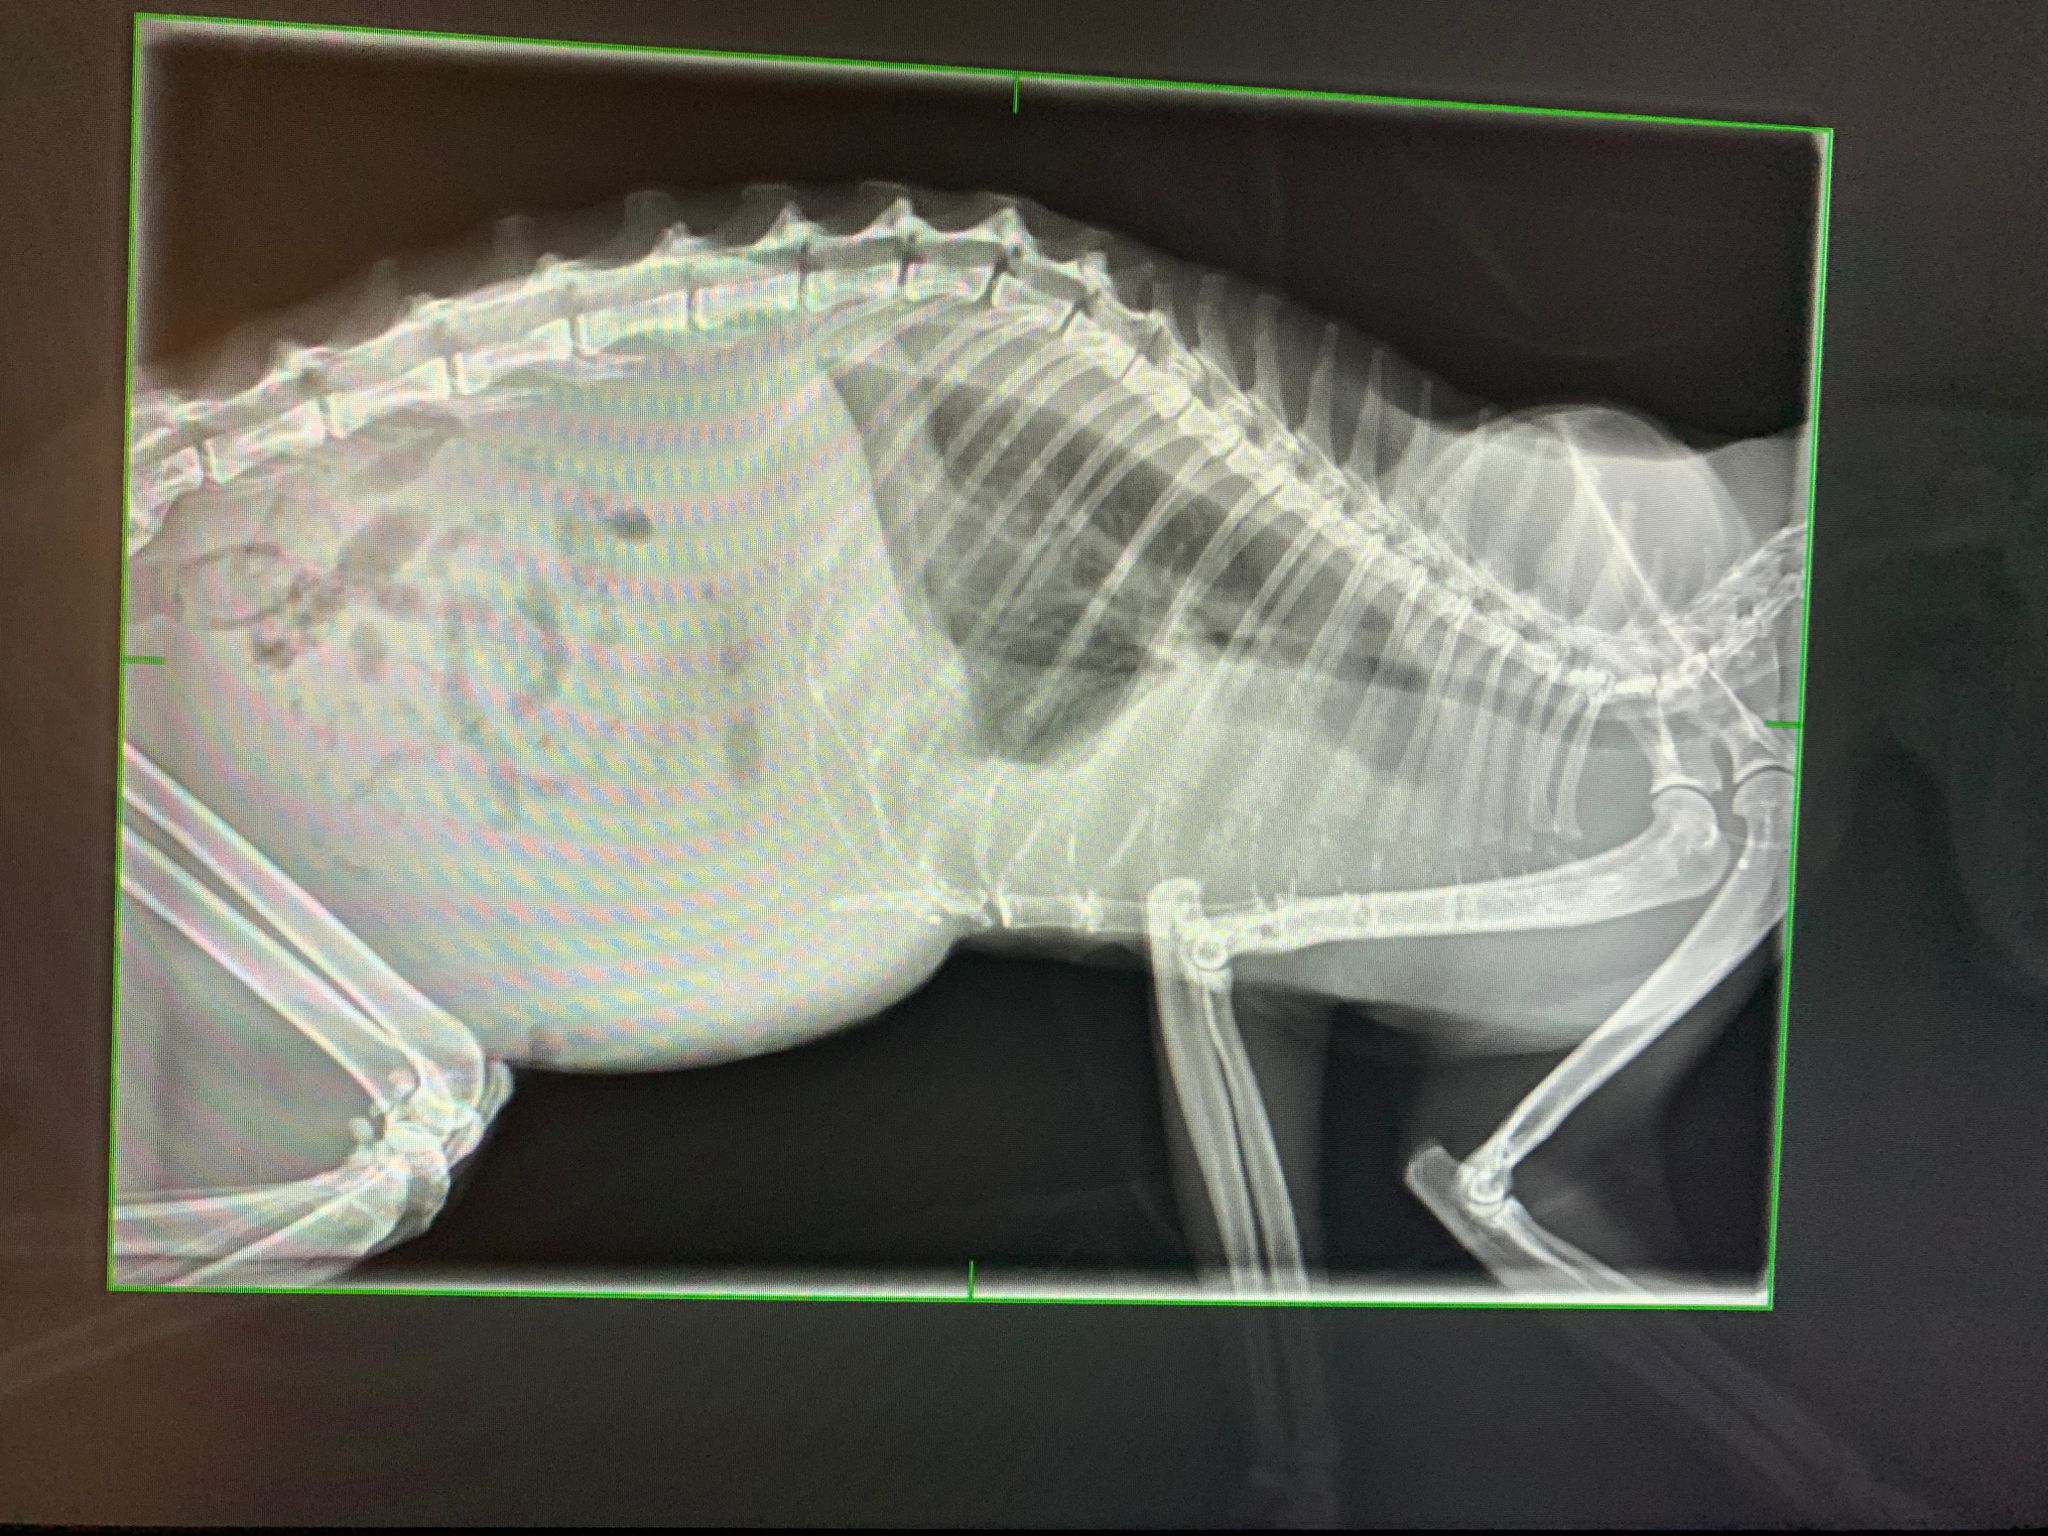

Her right side of mouth is surprisingly ok, left side of her mouth is really bad, esp the bottom teeth, root alr exposed. So will be in pain, that’s why her left side eye discharge is more also. Gum v pale. All point to anaemic. Got heart mur mur, soft one. I didn’t request to take pro bnp cos I know and I know anemic will cause mur mur too. Physical examination can already feel: liver enlarged. Spleen extremely enlarged. Might be end stage lymphoma. if she can slot me in for u/s I’ll take. Meanwhile she help to take an X-ray to show me her huge spleen in her small body. she is v dehydrated also, so the previous 8/4 results of HCT 20% should be a false number, means she must be v anemic. have to be careful w fluid (she need but her anemic is contradicting.

Xray done: Got free fluid/ blood that cause her breathing to be like that. Something pushing her intestine to one side also. got fluid in lung too. Sigh.